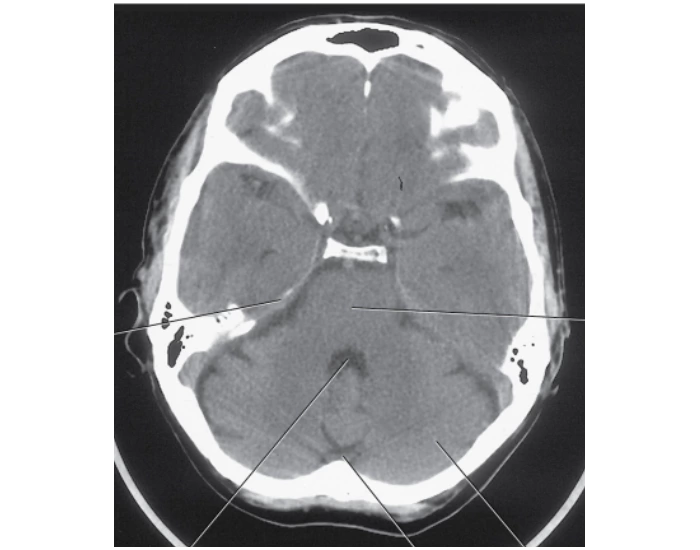

axial ct brain anatomy fourth ventricle

Axial CT Of Fourth Ventricle Diagram | Quizlet

3.14 Axial CT Of Fourth Ventricle. Quiz